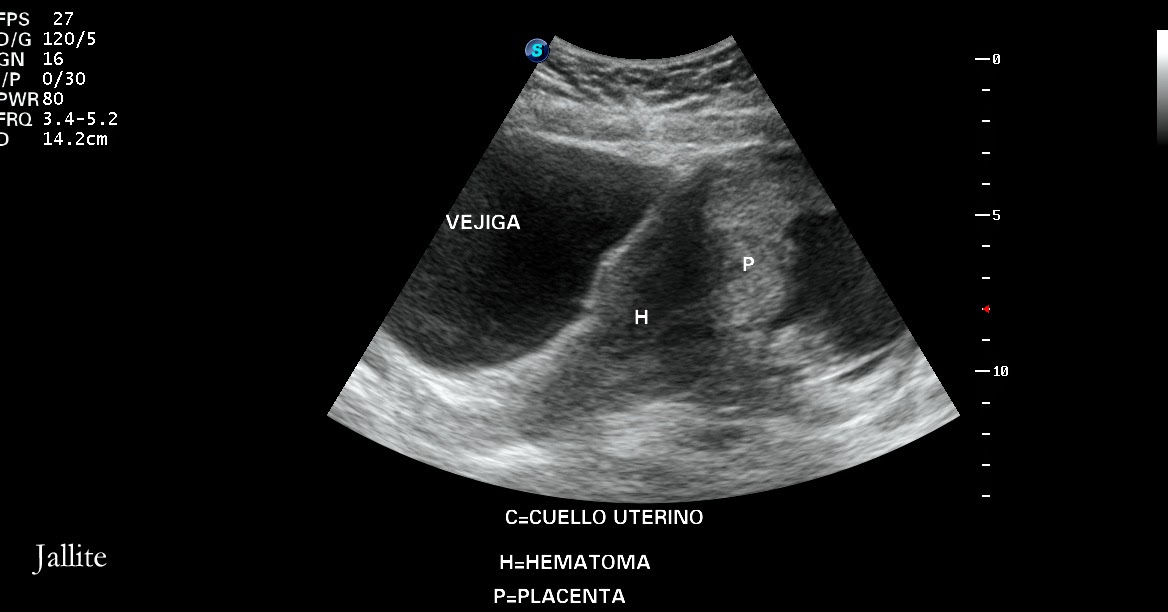

An ultrasonographic transvaginal scan image showing a placenta previa

An ultrasonographic transvaginal scan image showing a placenta previa Speculum Exam In Placenta Previa Placenta previa refers to the presence of placental tissue that extends over the internal cervical os. However, digital examination should not. Describe the management of patients with placenta. Describe the pathophysiology of placenta previa. Describe the risk factors for placenta previa. Placenta that extends near, partially over, or beyond the internal cervical os. Any pregnant woman beyond the first trimester. Speculum Exam In Placenta Previa.